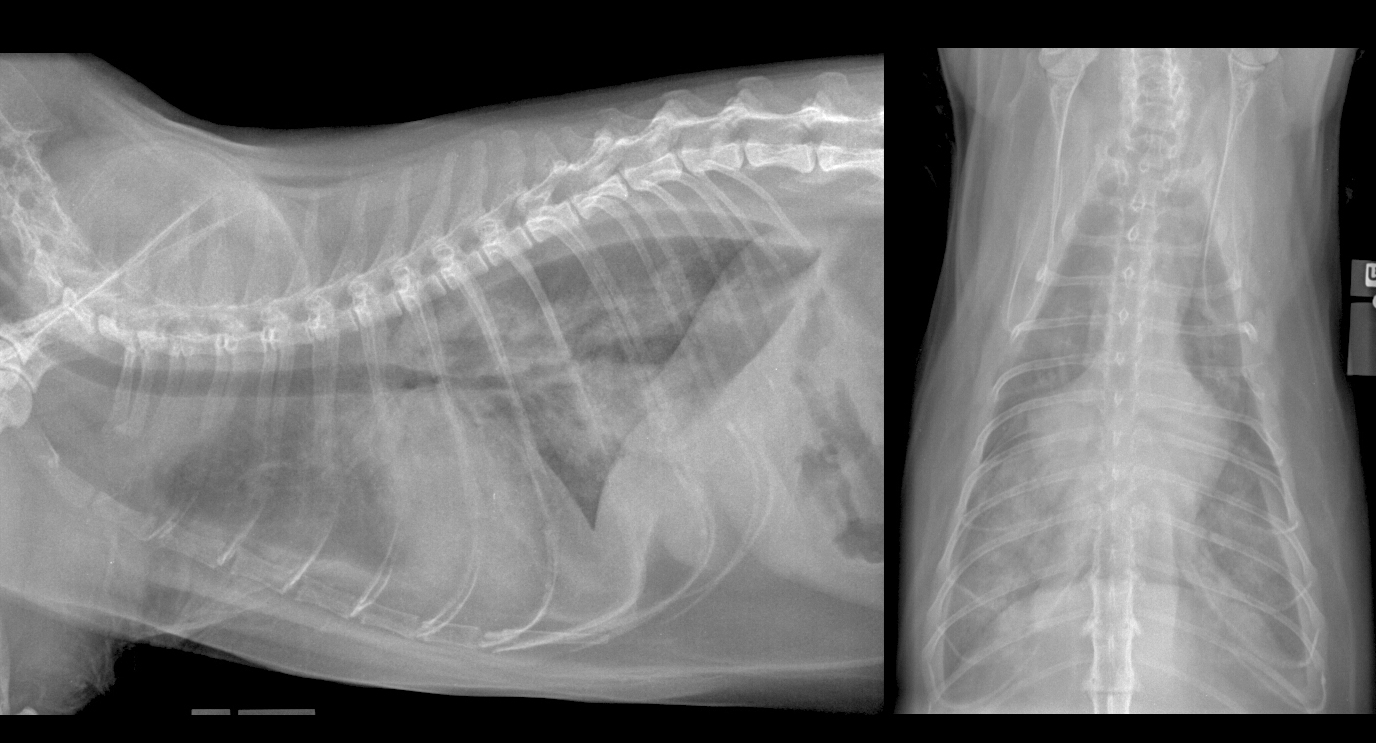

Histoire clinique: Chat mâle domestique opéré de 4 ans, présenté pour difficulté respiratoire.